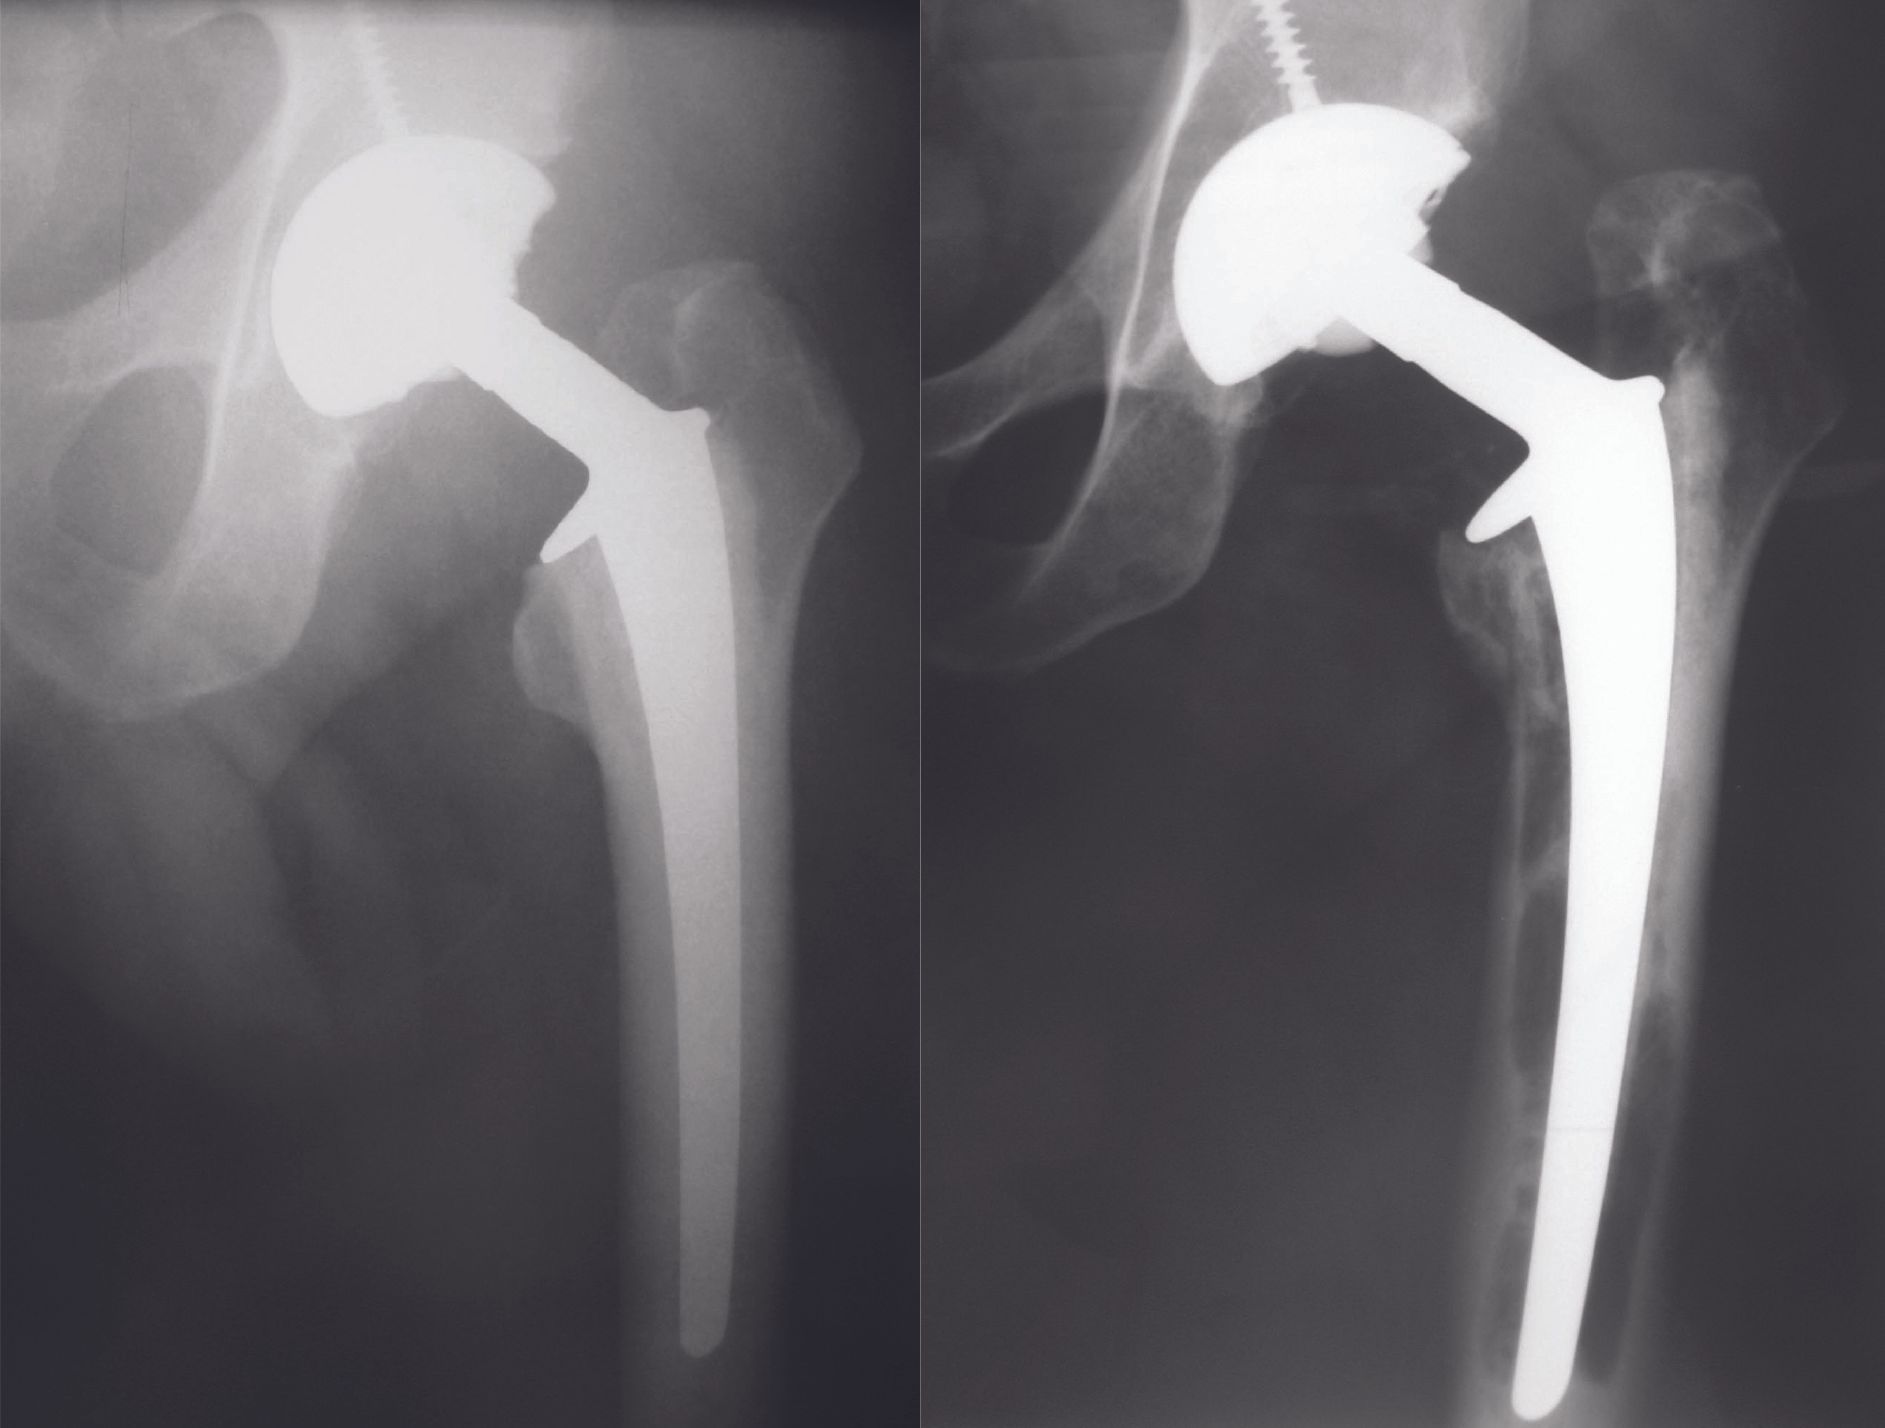

One-piece femoral stems pose different problems in reproducing the morphology of these vara hips, even though their use appears to be safer. Massin et al [8] have shown that with a set of 15 implant sizes, with 3 different metaphyseal configurations and 2 neck-shaft angle options, offset could be restored at the planning level in 86% of cases. However, the stock of implants required is very large and not in line with the current trend of cost optimization. In addition, there are still 14% of hips that do not have an anatomical reconstruction. Finally, this is only based on planning data and has not been proven in practice. In addition, the use of pins with increased femoral offset has frequently resulted in reduced arthroplasty survival compared to the same standard implants due to excessive stress on the femoral fixation. For example, we have found that femoral implants with varied necks (Lubinus SP2 117°) reproduce the anatomy of coxa vara hips better than standard implants, but are more prone to femoral loosening (7% at 6 years' follow-up, Fig. 3) and do not prevent dislocation (5.4%) [9].

[9] Bachour F, Marchetti E, Bocquet D, Vasseur L, Migaud H, Girard J. Radiographic preoperative templating of extra-offset cemented THA implants: how reliable is it and how does it affect survival? Orthop Traumatol Surg Res 2010;96:760-8.